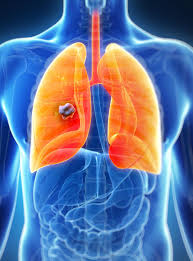

Congestie in termografia utilizează imagini termice care detecteaza noi vase de sange si modificarile chimice. Cancerul pulmonar este principala tumoră umană ca și mortalitate, atât la bărbați, cât și la femei, în întreaga lume. Afla totul despre cancerul pulmonar de pe doc.ro: Medicii recomandă să vă prezentaţi imediat la medic dacă aveţi în mod. Celulele canceroase se vor grupa si vor forma o tumora pulmonara. Cancerul pulmonar este definit ca fiind o reproducere necontrolata a unor celule anormale in interiorul plamanului. Celulele anormale nu îndeplinesc funcția celulelor pulmonare. Ce opțiuni noi de tratament au pacienții diagnosticați cu această boală?

Celulele canceroase se vor grupa si vor forma o tumora pulmonara. Cancerul pulmonar este principala tumoră umană ca și mortalitate, atât la bărbați, cât și la femei, în întreaga lume. Tuse persistenta timp de luni; Pot fi grupate in simptome toracice, extratoracice nemetastatice, extratoracice metastatice si generale. Dacă vorbim despre imaginea clinică, este complet diferită în fiecare caz.